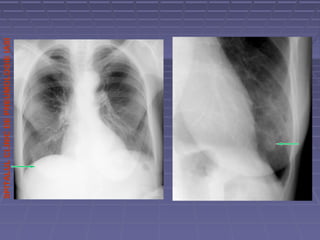

Pectus excavatumPectus excavatum

Cord deplasat spre stingaCord deplasat spre stinga

Arie de crestere a densitatii pulmonare datorita comprimarii plaminuluiArie de crestere a densitatii pulmonare datorita comprimarii plaminului

de catre sternul deformatde catre sternul deformat

 Pectus excavatum asimetric(torace in pilnie)